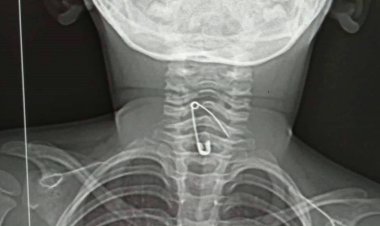

নুডলস খেতে গিয়ে শিশুর গলায় আটকে গেল সেফটি পিন

বর্তমানে শিশুটি হাসপাতালের ৩৩ নম্বর ওয়ার্ডে চিকিৎসাধীন। উন্নত চিকিৎসার জন্য তাকে...